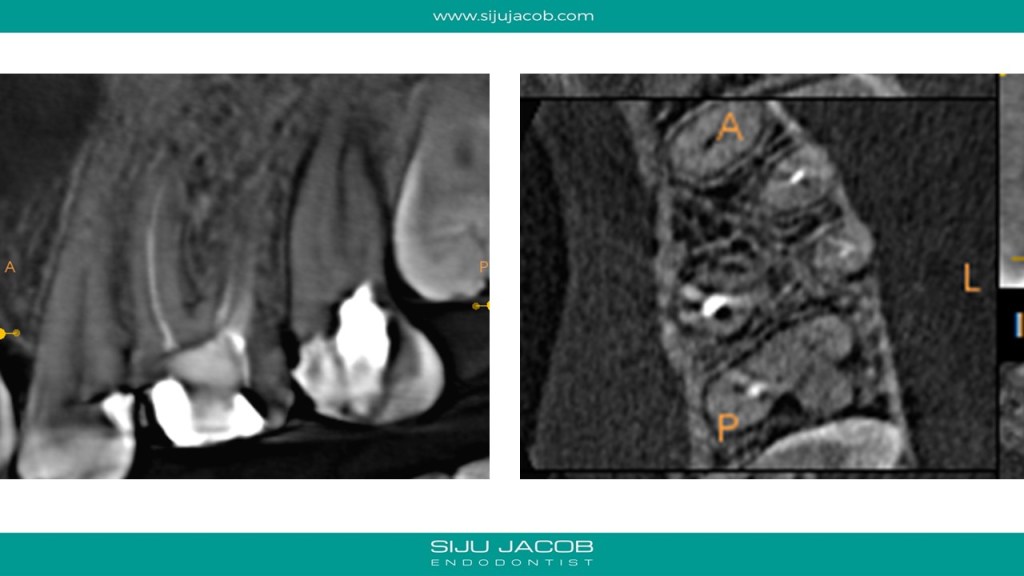

Some cases are such that when you eventually finish, you wonder what the fuss was all about. I struggled to locate the canals in this case. Not sure why. Yes, the access was difficult, but the main reason I struggled was probably the prior access that was made. This made me lose orientation initially. I managed to locate one canal and then took an Inter-appointment CBCT. This made things much easier. More in the short video below:

And below are the clinical slides of the same case: